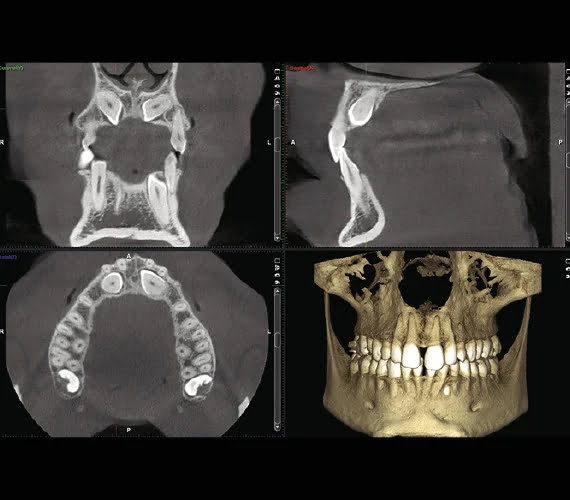

Dzięki inteligentnym rozwiązaniom, algorytmom i zaawansowanej technologii wszystkie nasze stomatologiczne aparaty do obrazowania 3D zapewniają proste, wyraźne i wysokiej jakości obrazy nawet przy niskiej dawce promieniowania. Urządzenia zostały zaprojektowane w celu wyeliminowania czynnika ludzkiego podczas obrazowania CBCT. Użytkownicy mają dostęp do takich opcji jak kompensacja ruchu pacjenta, tłumienie artefaktów i redukcja szumów.

Nasz unikalny protokół obrazowania Planmeca Ultra Low Dose™ to zaawansowana metoda uzyskiwania aktywnych obrazów 3D przy niskiej dawce promieniowania. W rezultacie można uzyskać znacznie więcej informacji niż w przypadku konwencjonalnych zdjęć panoramicznych 2D, bez statystycznego obniżenia jakości obrazu, nawet gdy dawka promieniowania dla pacjenta jest taka sama lub niższa, co zostało udowodnione w różnych badaniach naukowych.

Wszystkie nasze urządzenia 3D pozwalają na swobodny wybór wielkości voxela, rozdzielczości i wartości ekspozycji – zarówno dla zdjęć CBCT, jak i panoramicznych 2D, zdjęć Planmeca ProFace®, skanowania modeli 3D, śledzenia szczęki i wielu innych. Może również wykonywać diagnostykę według specjalistycznych protokołów, co ułatwia dostosowanie pracy do docelowego obszaru i wielkości.